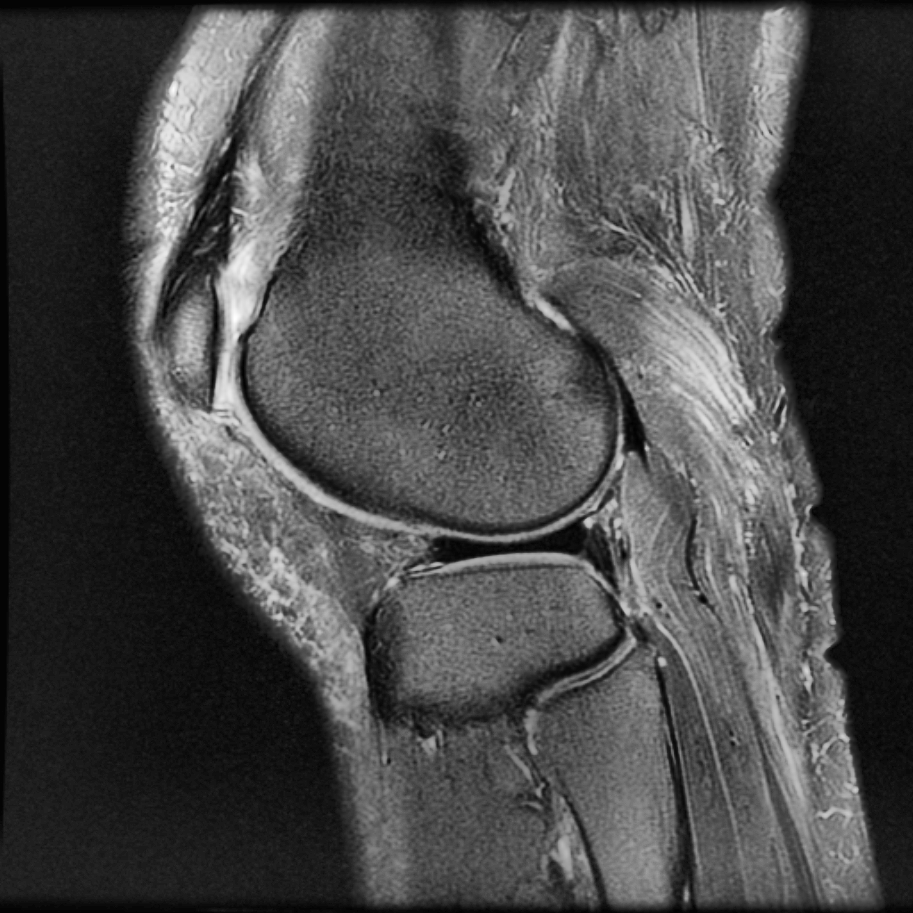

以上是直方图均衡Histogram Equalization的简单应用。事实上,HE最初用在医疗图像上。以下图为例:

如果只应用简单的HE,结果如图:

尽管组织“点亮”了,但底噪一样被“点亮”了。

MATLAB内置了adapthisteq函数,可以实现CLAHE算法。我们以Human Knee为例,看看CLAHE效果:

不仅目标被点亮了,而且低噪也被抑制了!